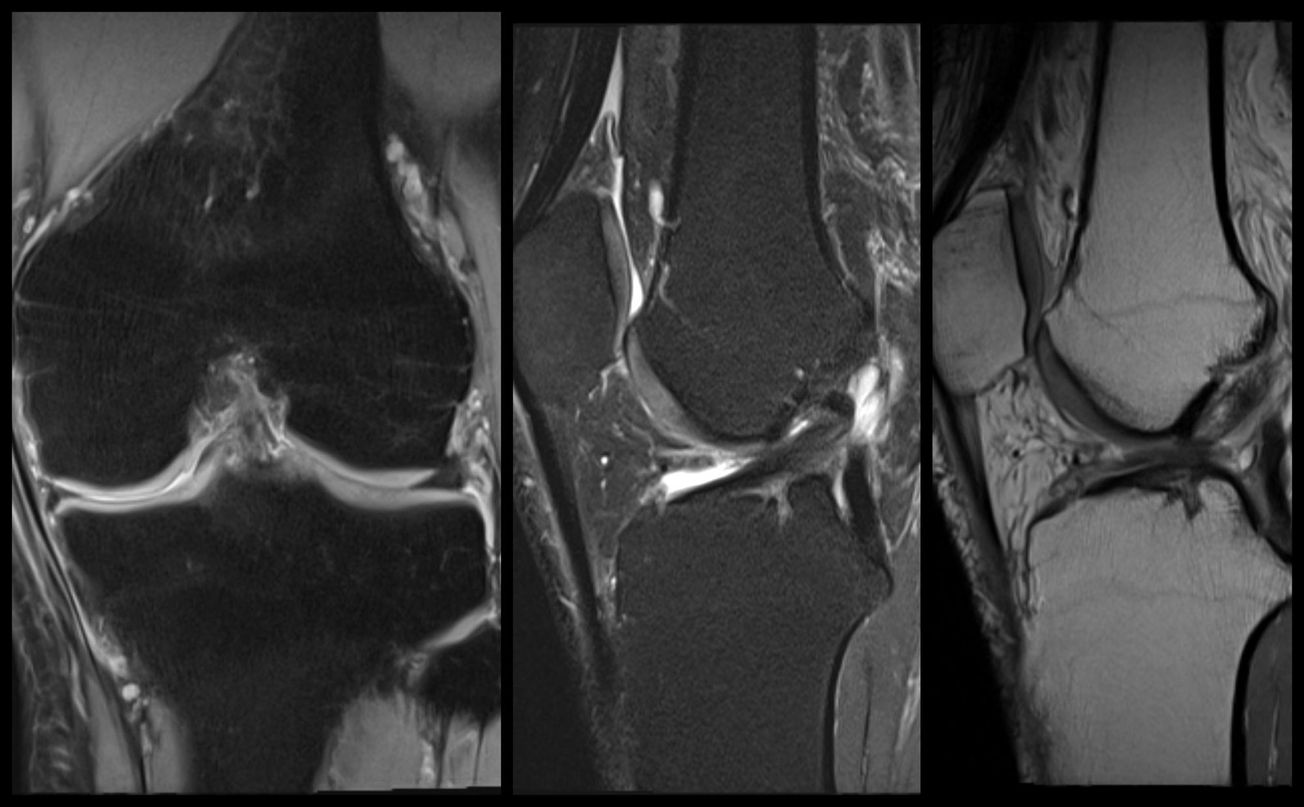

Joints Total Knee Arthroplasty (Cementless, Robotic-assisted) , and D. Gordon Allan , and James Lieber April 16, 2023